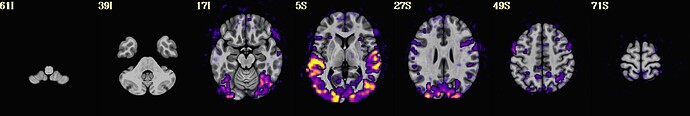

So far, code below can produce images like displayed below :

@chauffeur_afni                                                 \

-ulay ${background}                                     \

-ulay_range "2%" "98%"                                  \

-olay ${tempFolder}/meanInputDataSet+tlrc               \

-func_range_perc_nz 1                                   \

-set_subbricks 0 0 0                                    \

-box_focus_slices ${tempFolder}/meanInputDataSet+tlrc   \

-cbar "Reds_and_Blues_Inv"                              \

-pbar_saveim       ${tempFolder}/color_bar              \

-opacity 4                                              \

-prefix  $tempFolder/tempPlots                          \

-thr_olay 0                                             \

-save_ftype JPEG                                        \

-montx 9 -monty 1                                       \

-montgap 3                                              \

-set_xhairs OFF                                         \

-pbar_posonly                                           \

-label_mode 1 -label_size 3